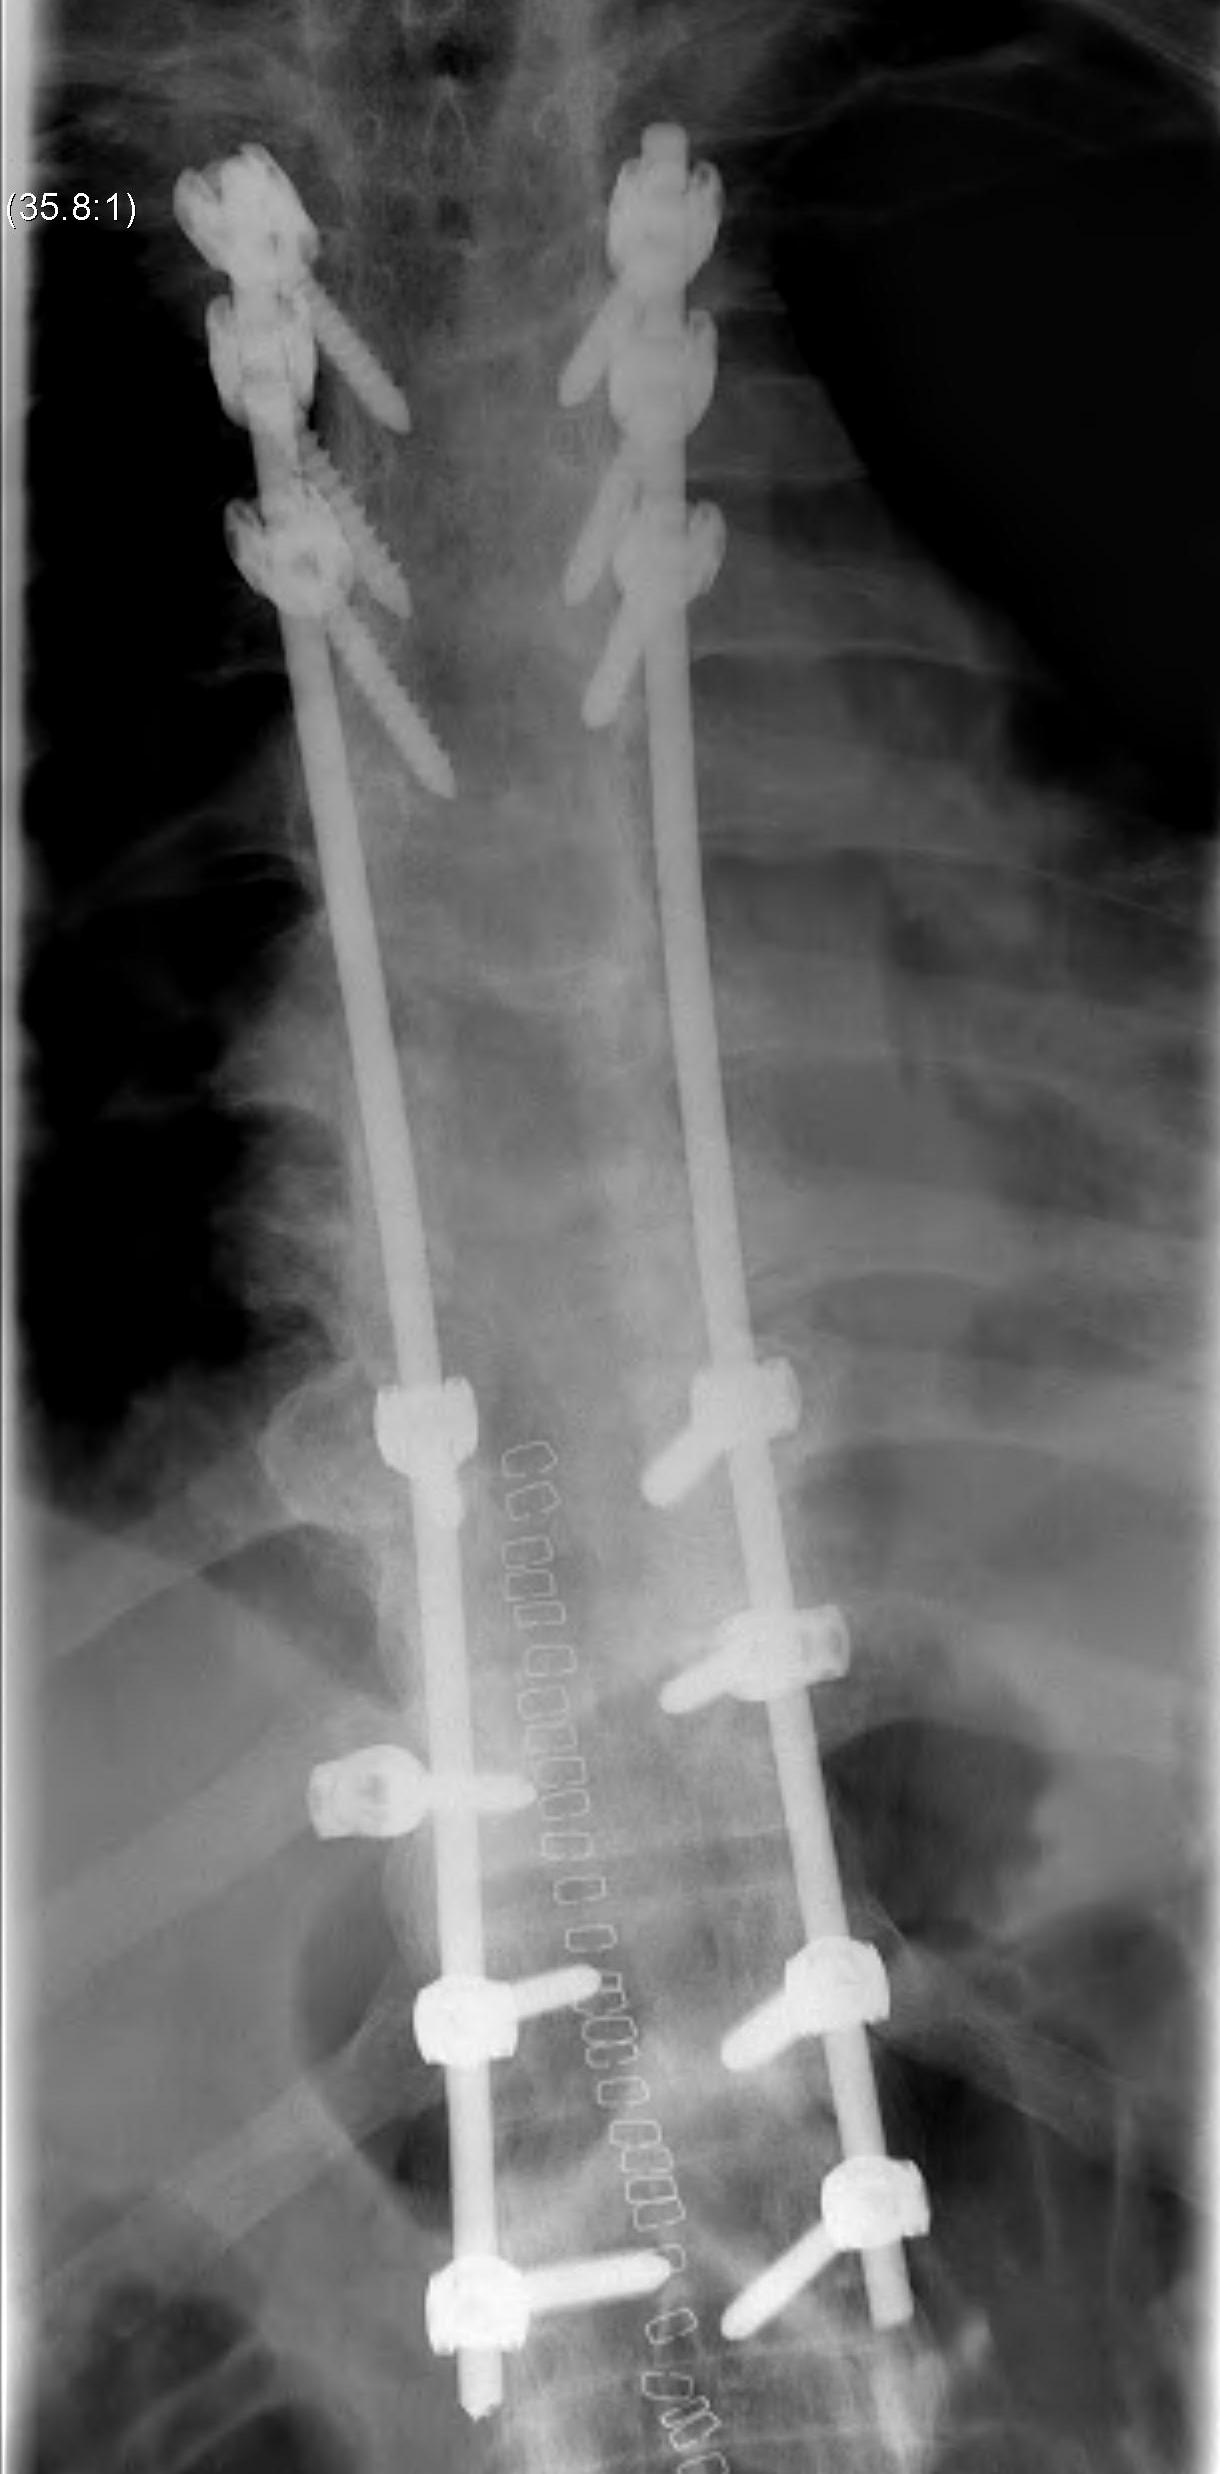

B. Thoracolumbar

Options

Smith-Peterson Osteotomy with instrumentation

- osteotomies in SP above & below central vertebra

- centre of correction is disc / must be healthy

- 10o per level / maximum 30o

- major risk is to aorta

Pedicle subtraction osteotomy

- 30 - 40o per level

- centre of correction vertebral body

- more dangerous / increased correction with better union